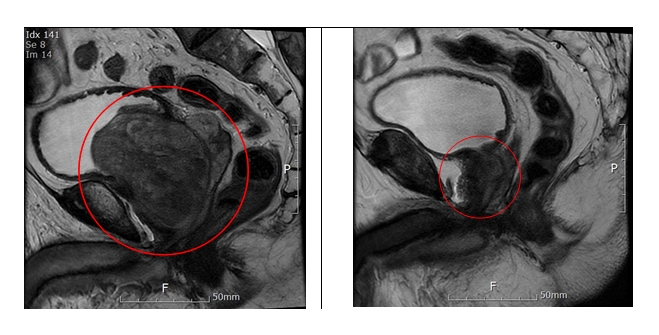

[로이슈 임한희 기자] 차의과학대학교 분당차병원(원장 김재화) 비뇨의학과 박동수 교수팀은 비대증으로 인해 정상수준의 10배 이상 커진 전립선(160g)에서 발견된 암을 로봇수술로 제거하는데 성공했다고 17일 밝혔다.

박교수팀은 배뇨장애로 병원을 찾은 81세 환자의 복부에 다빈치로봇으로 6개의 작은 구멍을 뚫어 악성종양 5개를 제거했다. 박교수팀은 종양이 포함된 전립선 전체와 종양을 둘러싼 림프절 등을 완전히 제거하는 근치적 전립선 적출술로 집도했다.

수술 받은 환자의 전립선은 전립선비대증으로 인해 일반 남성의 전립선 크기(15-20g)보다 8~10배 큰 상태였다. 초대형 전립선 환자의 경우 혈관이 매우 발달해 수술 시 극심한 출혈이 생길 수 있고, 해부학적 파악이 힘들어져 수술에 큰 어려움이 따른다.